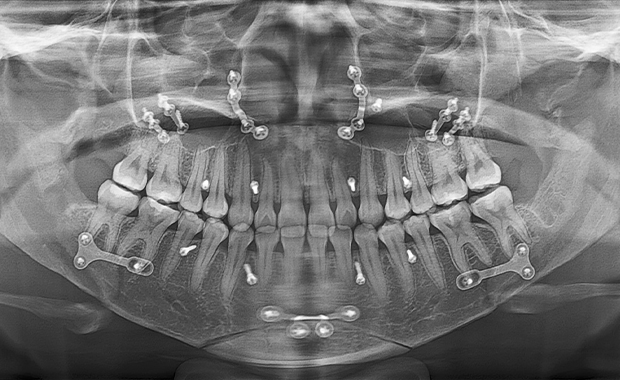

얼굴 턱뼈 수술에서는 절단 후 분리된 뼈를

새로운 위치에 고정하기 위해 고정핀을 사용합니다.

이 핀은 뼈가 충분히 회복된 후, 핀제거 수술을 통해 제거할 수 있습니다.

• X-ray, CT 등

방사선 촬영에서 핀이

보이고 싶지 않은 경우